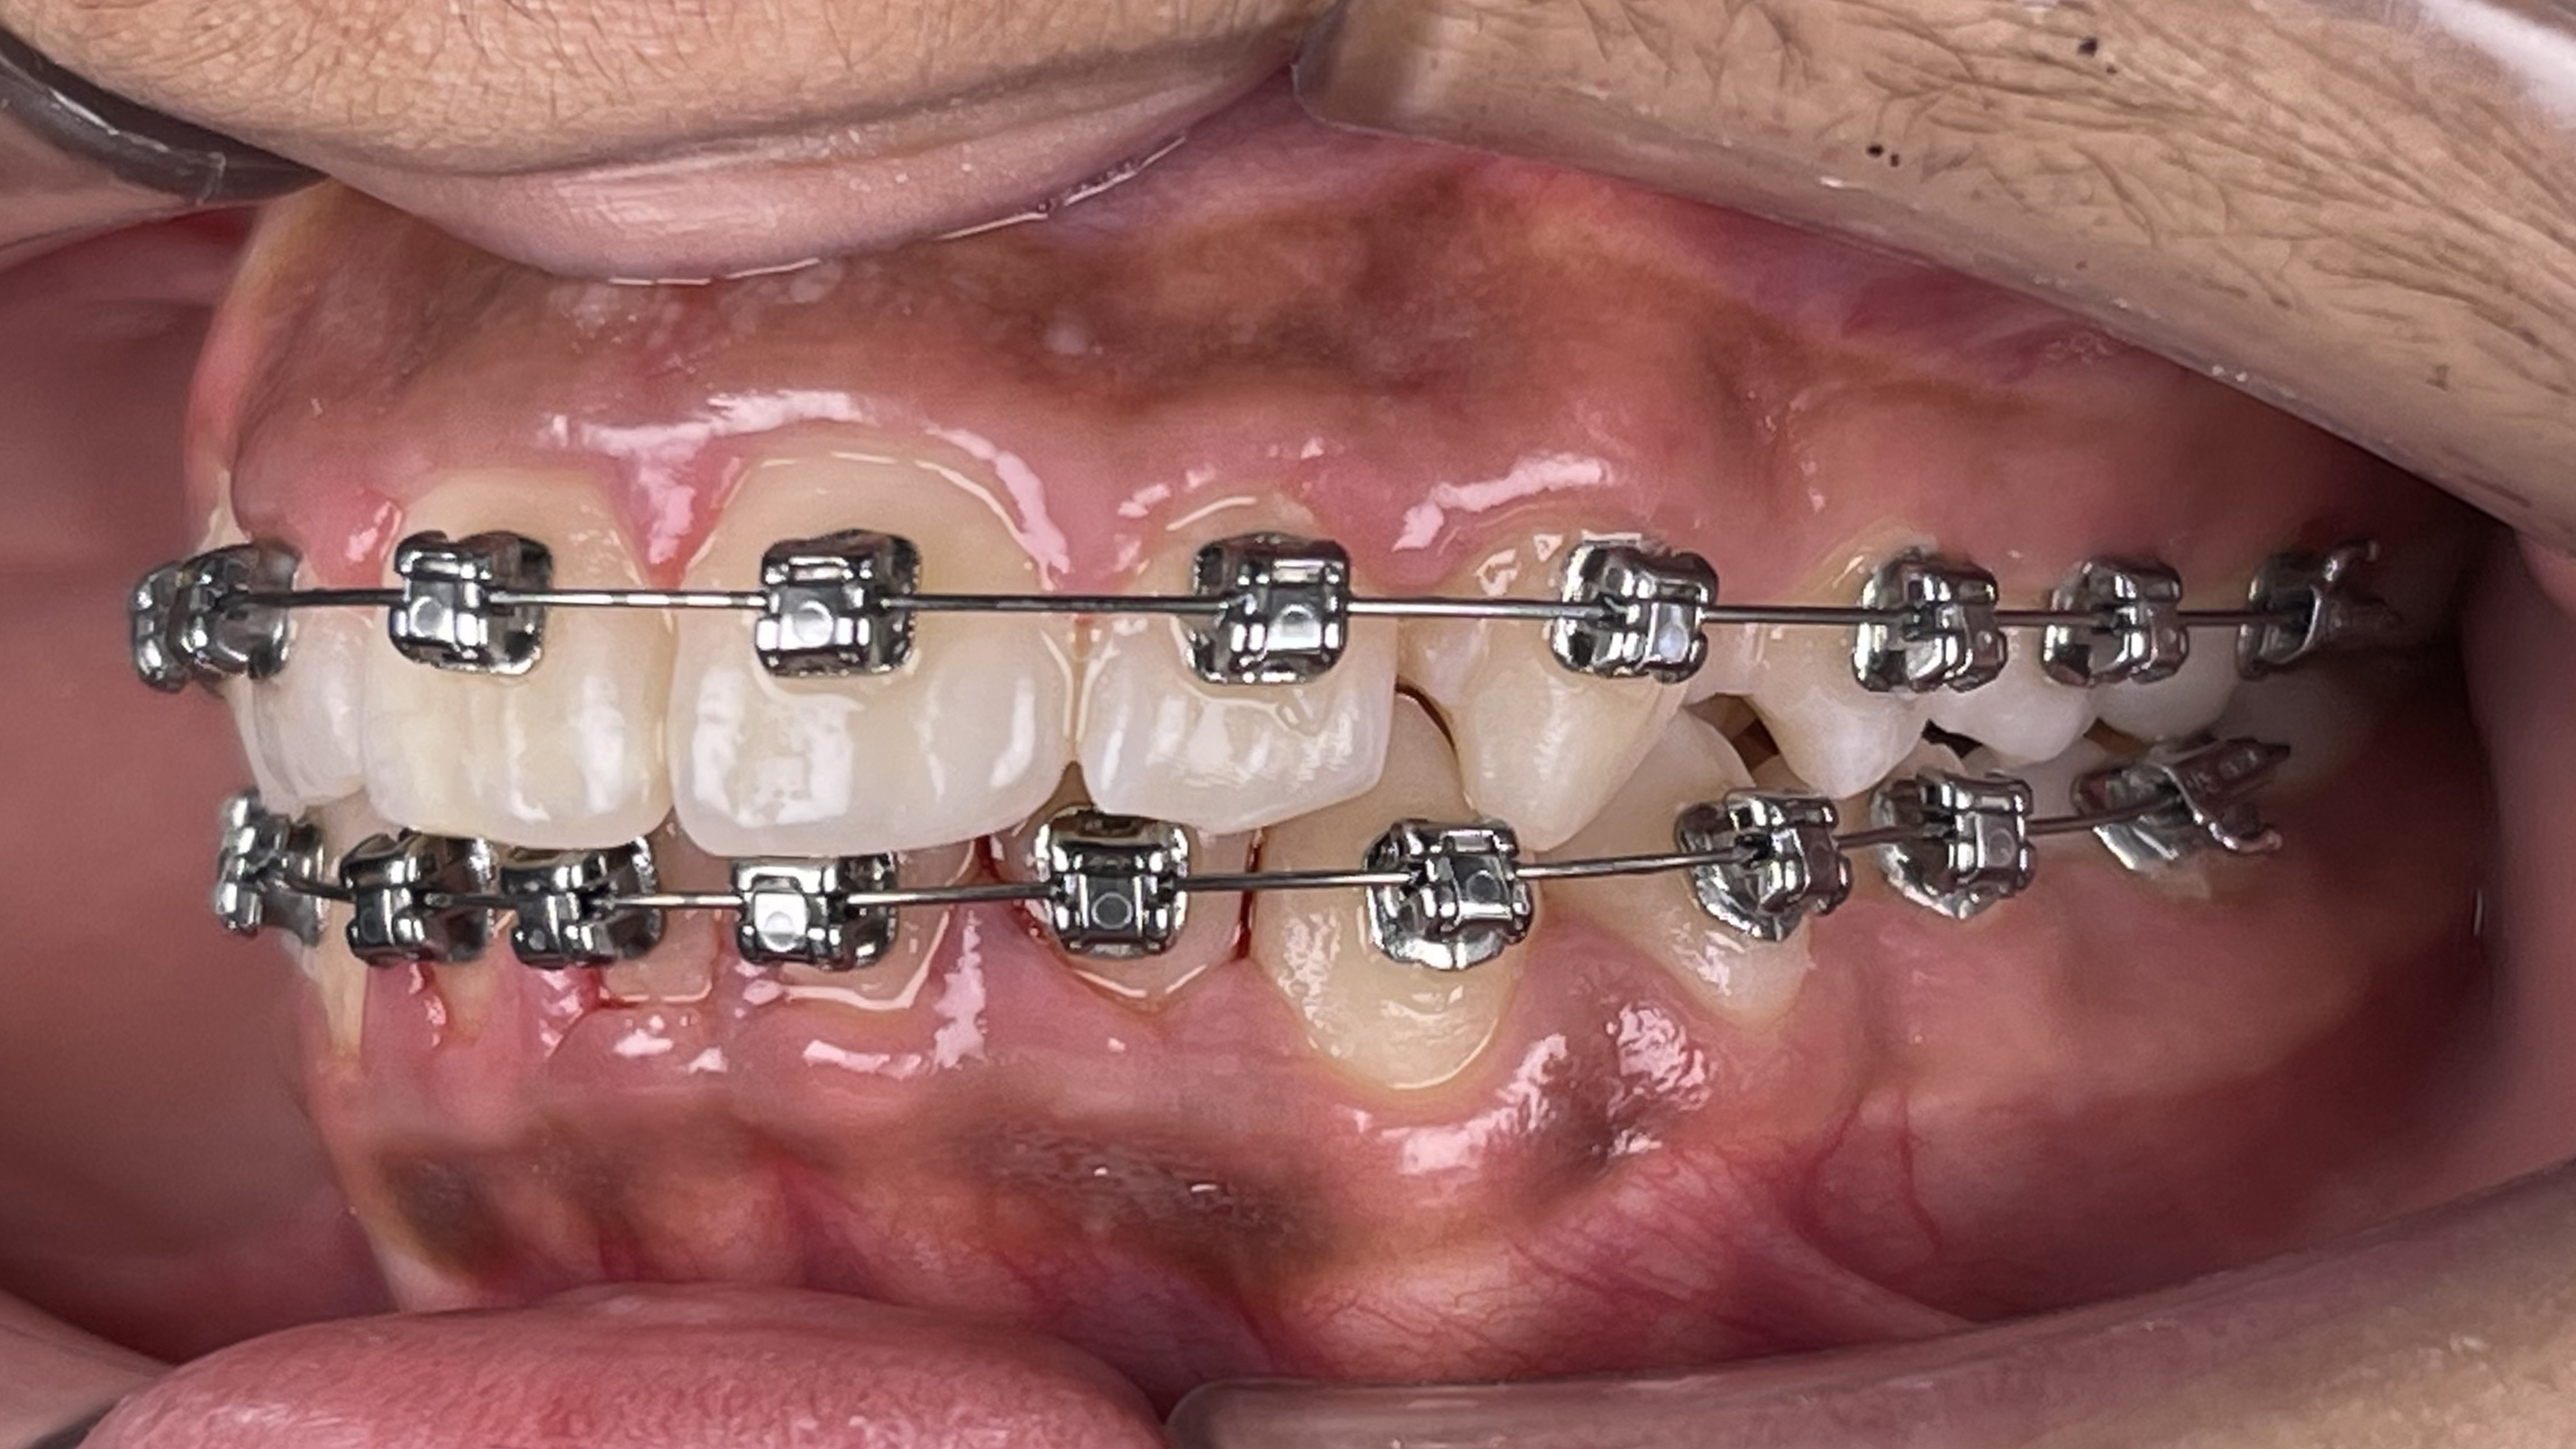

Smiles Gallery

We love to see our patients smile! Here are some of our best before-and-after pictures,

all in one fantastic Smile Gallery